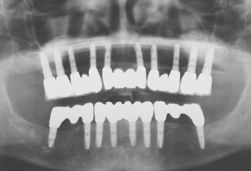

Zahnimplantate bei schwierigen Voraussetzungen

Zahnimplantate sind "in aller Munde". Vom Ersatz einzelner fehlender Zähne bis zum kompletten Zahnersatz beim zahnlosen Patienten werden heute viele Probleme in der Zahnmedizin mit Implantaten gelöst. Aber was, wenn der Patient ungünstige Voraussetzungen hat, zum Beispiel kaum...

Implantate und Knochenaufbau: Abwägung zwischen verschiedenen Knochen

Seit rund 30 Jahren ist es möglich, verlorene Zähne durch Implantate zu ersetzen und damit für den Patienten Komfort und Sicherheit gegenüber konventionellen Lösungen deutlich zu verbessern. In den ersten Jahren ihres Einsatzes lag die größte Schwierigkeit darin, dass Implantate nur...

Schnelle und zuverlässige Hilfe bei zahnlosem Kiefer

Obwohl sich viele Menschen heute intensiver um Mundgesundheit und Zahnhygiene kümmern, sind lückenhafte Gebisse keine Seltenheit. Während bei einzelnen Zahnlücken eine Therapie mit modernen Zahnimplantaten meistens Erfolg verspricht, haben Patienten mit einem fast oder gänzlich...